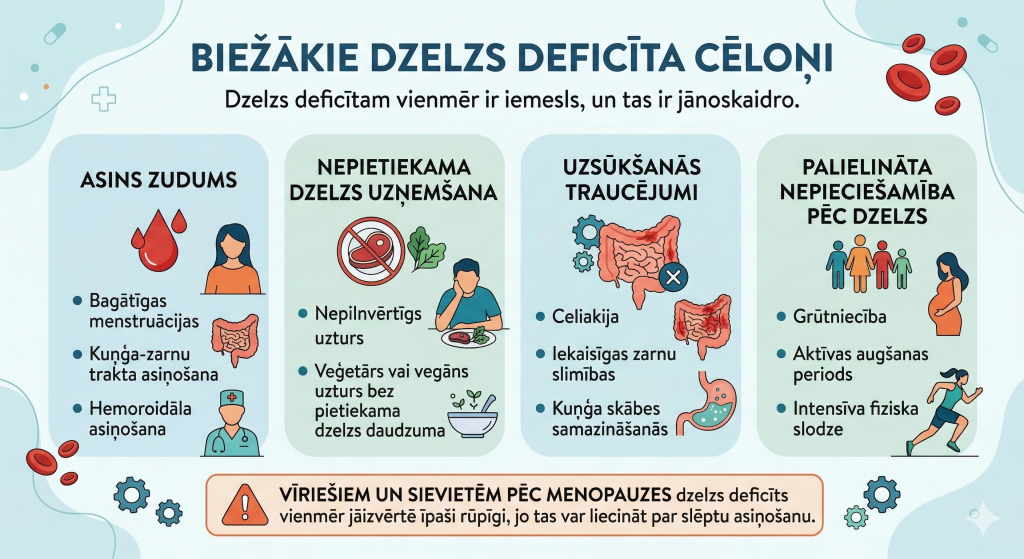

Biežākie dzelzs deficīta cēloņi

Dzelzs deficītam vienmēr ir iemesls, un tas ir jānoskaidro.

Biežākie cēloņi ir:

Asins zudums:

- bagātīgas menstruācijas

- kuņģa-zarnu trakta asiņošana

- hemoroidāla asiņošana

Nepietiekama dzelzs uzņemšana:

- nepilnvērtīgs uzturs

- veģetārs vai vegāns uzturs bez pietiekama dzelzs daudzuma

Uzsūkšanās traucējumi:

- celiakija

- iekaisīgas zarnu slimības

- kuņģa skābes samazināšanās

Palielināta nepieciešamība pēc dzelzs:

- grūtniecība

- aktīvas augšanas periods

- intensīva fiziska slodze

Vīriešiem un sievietēm pēc menopauzes dzelzs deficīts vienmēr jāizvērtē īpaši rūpīgi, jo tas var liecināt par slēptu asiņošanu.